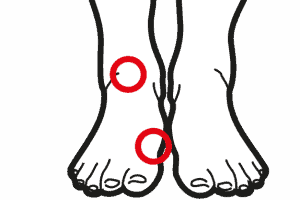

Gonartrosi femoro tibiale

Il ginocchio è una struttura complessa e fondamentale del nostro corpo. Collega la coscia e la gamba, permettendoci di muoverci liberamente. La cartilagine articolare svolge un ruolo primario in quest’area, proteggendo e ammortizzando le ossa degli arti inferiori durante i movimenti. La struttura anatomica del ginocchio Il ginocchio si compone di due articolazioni principali: la prima … Continued